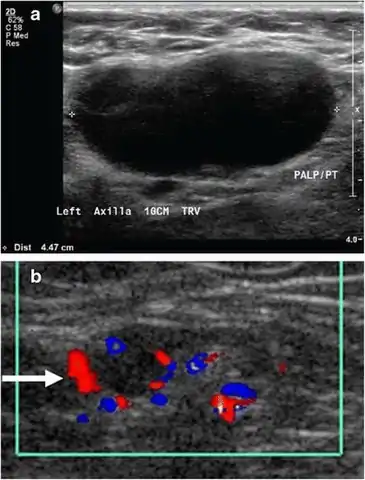

Absence of flow and hyperechogenic content in deep vein thrombosis of the subsartorial vein

Superficial soft tissues

Doppler ultrasonography can help distinguishing benign from malignant soft tissue lumps.[15] Power Doppler is useful in assessing tendon and joints inflammation such as paratenonitis.[16]

15. 1 2 Dialani V, James DF, Slanetz PJ (April 2015). "A practical approach to imaging the axilla". Insights into Imaging. 6 (2): 217–29. doi:10.1007/s13244-014-0367-8. PMC 4376818. PMID 25534139. Creative Commons attribution license